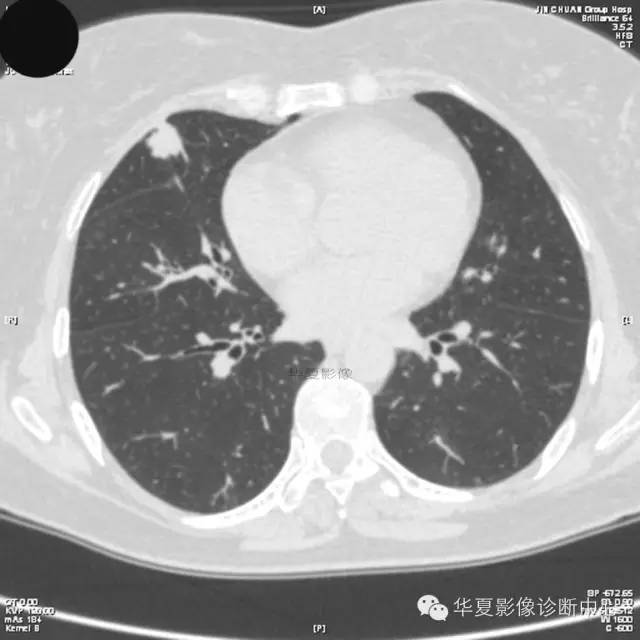

【病例学习】典型周围型肺癌CT病例一例

女,56岁,其父因肺癌去世,自觉胸部疼痛不适来诊要求拍胸片。

1.右肺上叶:肺组织1块,大小13×4×7cm。切面棕红色。2.右肺上叶肿物:灰白色组织一块,大小3×1×1.5cm。切面灰白色。3.右肺中叶结节:灰白色绿豆大组织1块。4.淋巴结:灰黑色绿豆大组织1块。

(右)肺中分化鳞状细胞癌。浸及胸膜。支气管残端切净。淋巴结未见癌转移(0/10)。